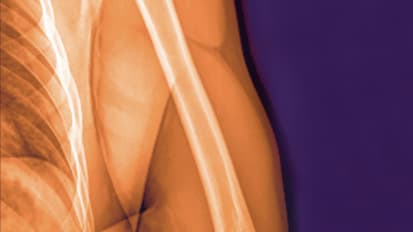

The two-time Cy Young award winner will undergo Tommy John surgery to repair an ligament tear in his elbow.

Tears or ruptures of the ulnar collateral ligament (UCL) are the most common elbow injury among baseball players from youth leagues to the major leagues, especially pitchers. The most severe cases require reconstructive surgery, commonly known as Tommy John surgery for the Los Angeles Dodgers pitcher who was the first to have the procedure in 1974.